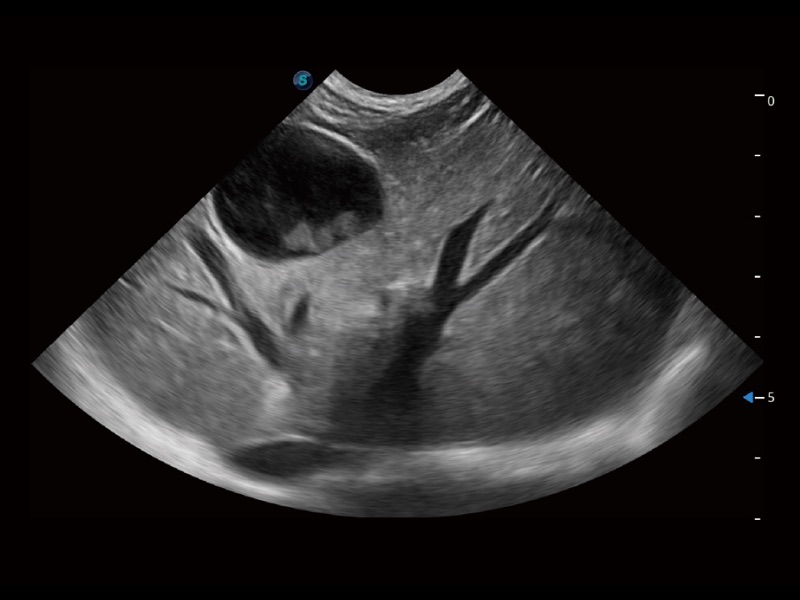

(猫)胆囊

(犬)四腔心

(犬)肝脏